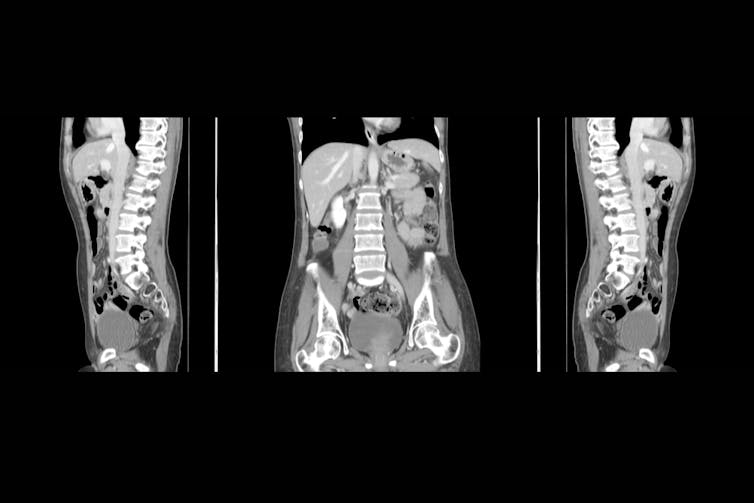

Computed tomography (CT)

This technique uses an x-ray beam to produce cross-sectional images of the human body. When the imaging process is taking place, the x-ray tube continuously emits an x-ray beam and is rotating in a 360 degree circle in a device called a gantry.

While this is happening, the patient is lying on a special CT imaging table that is allowing the x-ray beam through. The x-ray beam is shaped similar to a hand-held fan and is often described as a fan beam. There are multiple digital detectors located within this circular gantry that continually identify the energy of the x-ray photons that exit the patient.

The motion of the table and patient moving through the gantry allows images to be reconstructed as slices (or tomographs) of human tissue. The most common CT exam is to scan a patient’s chest, abdomen and pelvis, and the most common reason for this is to identify the spread of cancer. “X-ray dyes” are injected into patients to identify cancer when using CT imaging, as the cancer tissue will absorb the “x-ray dye” and be more obvious on the image.

With routine CT imaging techniques, there should not be any risks or danger to patients from the levels of radiation used.